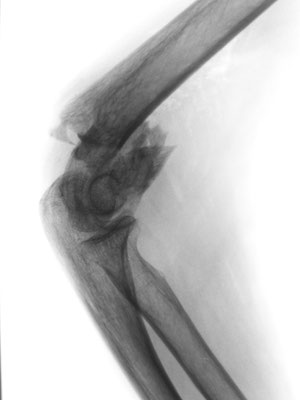

Ellenbogennaher Oberarmbruch/suprakondyläre Oberarmfraktur

Diese Brüche gehen häufig mit einer erheblichen Zertrümmerung des Knochens einher. In den meisten Fällen ist auch die Gelenkfläche betroffen, so dass eine operative Rekonstruktion erforderlich ist. Wie bei allen gelenknahen Knochenbrüchen besteht die Aufgabe darin, ein sehr kurzes Knochenfragment an dem Schaftknochen zu befestigen und die Gelenkfläche stufenlos wieder herzustellen. In der Standardtechnik werden dabei zwei Platten benutzt. Dabei geben insbesondere die winkelstabilen Titanplatten optimale Möglichkeiten um die kleinen Knochenteile stabil zu befestigen.

Ist allerdings die Gelenkfläche so stark zerstört, dass eine Rekonstruktion nicht möglich ist, bietet sich bei Patienten in höherem Lebensalter die Implantation einer Ellenbogenprothese an. Mit dieser ist eine gute Funktion zu erreichen.